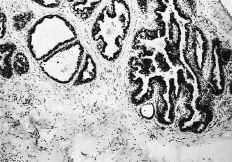

Las cuatro observaciones mostraron positividad a los RE con histocores superiores a 100. La evaluacion inmunomorfológica de los RE arrojó cifras de histocore hormonal (HH) comprendidas entre 108 y 300, con intensidades de ++/+++, en un porcentaje celular comprendido entre el 36 y el 75% (Figs. 1 y 2). La positividad a los RE se manifestaba por la presencia de inmunotinción especifica nuclear. En general, la positividad a los RE mostró un carácter de heterogeneidad de forma que no todas las áreas tumorales presentaban el mismo nivel de positividad o bien existían diferentes porcentajes en el número de núcleos marcados. En dos casos existían en periferia a las áreas tumorales imágenes de ginecomastia proliferativa, que asimismo mostraba positividad al receptor estrogénico (Fig. 3). En un caso (HH de 108) asimismo se cuantificaron en 230 fmol/mg ADN los REn mediante el método bioquímico DCC.

Fig. 2. Imagen microscópica del componente intraductal de uno de los casos estudiados mostrando positividad nuclear para los REn con un carácter heterogéneo. (ERICA, 400*.)